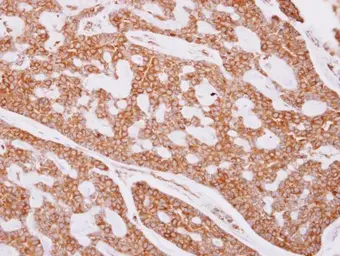

beta Tubulin antibody detects beta Tubulin protein at cytoplasm on human breast cancer by immunohistochemical analysis.

Sample: Paraffin-embedded breast cancer.

beta Tubulin antibody (GTX101279) dilution: 1:500.

Antigen Retrieval: Trilogy™ (EDTA based, pH 8.0) buffer, 15min